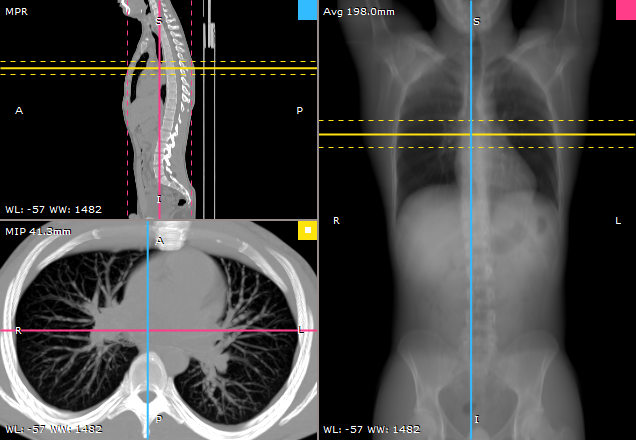

RadiAnt DICOM Viewer 内置的 3D MPR 工具可在任意平面(斜面)上重建图像,帮助实现仅凭基础图像无法实现的解剖结构可视化。